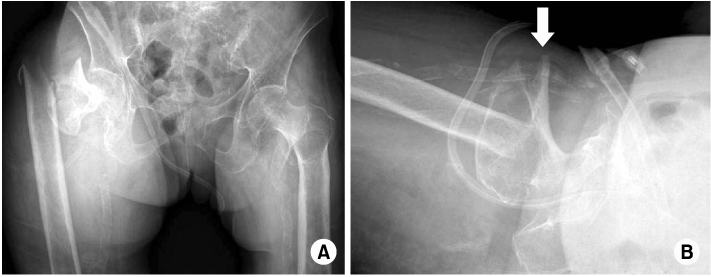

Fig. 3

Computed tomographic angiogram showing the extravasation of contrast material from branch of deep femoral artery.

Fig. 3 Computed tomographic angiogram showing the extravasation of contrast material from branch of deep femoral artery.